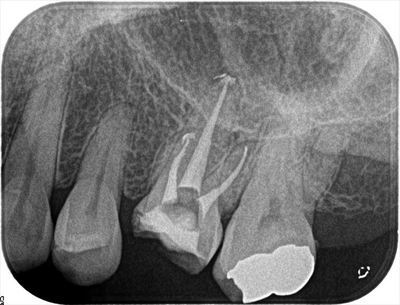

無事に3根管とも根尖まで攻略できました。

サーマフィルにて垂直加圧根管充填を行いました。

根管充填後のデンタルX線写真です。